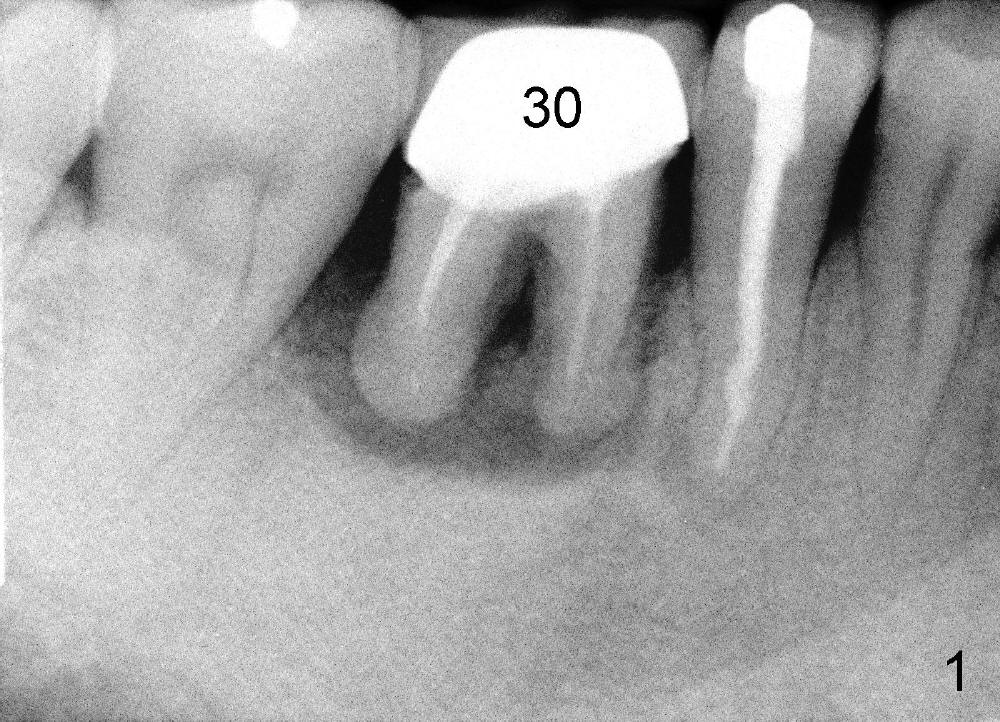

A 46-year-old man has severe periodontitis. The tooth #30 is complicated by incomplete root canal therapy (Fig.1,2). Three months after extraction (Fig.3-5: N: inferior alveolar canal), a 5x14 Tatum tapered implant is placed (Fig.6,7). The problem is that an implant driver is fractured (D in Fig.7), while the implant is being torqued. It takes time and effort to remove the fractured driver, but the implant is solid. The healing screw is placed without difficulty (Fig.8). Since the implant is placed lower than the lingual gingiva (L in Fig.9), a healing cuff is placed 1.5 months after implant placement (Fig. 10 and 11: C) to push the lingual gingiva down. The X-ray appears to show lower bone density around the implant (bone necrosis?), although the implant has no mobility at all. Since the implant is so solid, can we load it, two months after surgery? The lingual gingiva is now lower than the healing cuff (not shown). CT is scheduled to be taken tomorrow. Thanks.